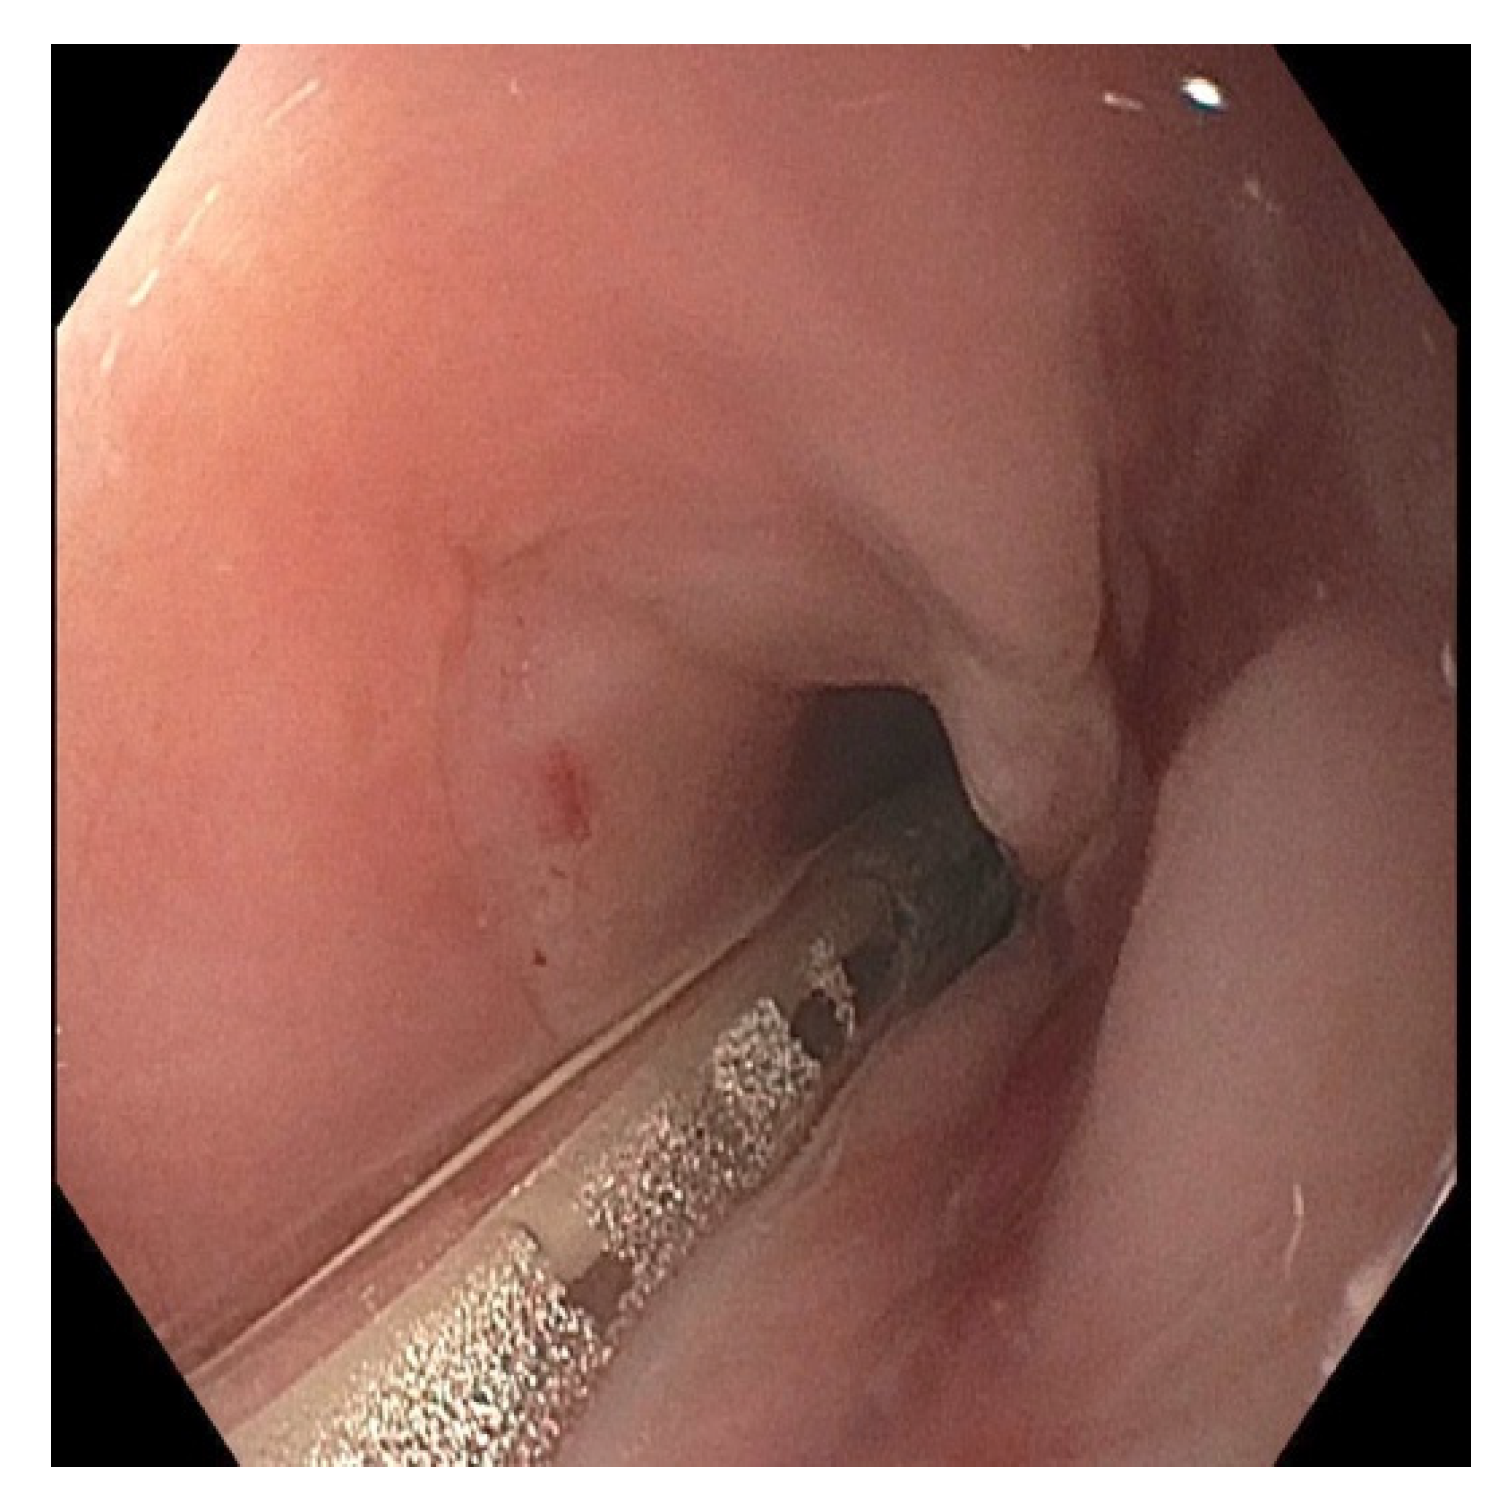

Endoscopic Evaluation for Stricture Formation Post Button Battery Ingestion

2. Case Presentation